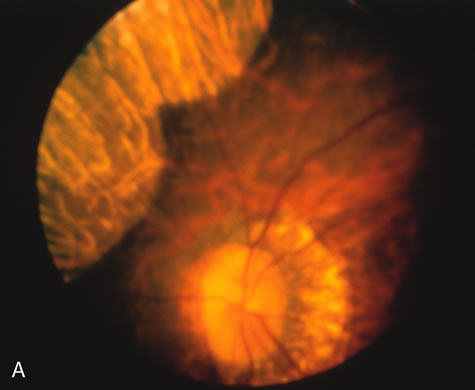

The carrier female with XLR RP, who has the golden tapetal sheen reflex, has normal FA findings. This suggests that the abnormal reflex is not due an abnormal pigment layer or deposition7 (Fig. 2A and B).

Fig. 2. Golden tapetal reflexes. There are three diseases in which there is an unusual golden reflex to the fundus: X-linked recessive RP in the carrier female, Oguchi's disease, and cone dystrophy. In all these diseases the angiogram is essentially normal, suggesting that this reflex is probably not related to pigment abnormalities. A, B. Carrier female of XLR retinitis pigmentosa. A golden scintillating reflex radiates from the macula. C, D. Oguchi's disease. A diffuse yellow metallic sheen is seen in the posterior pole (a pigmented chorioretinal lesion is an incidental finding). E, F. Progressive cone dystrophy. The typical bull's eye maculopathy is associated with a golden orange reflex.

In Oguchi's disease the hallmark fundus finding is a yellow metallic sheen (Fig. 2C). A similar sheen has been seen in progressive cone dystrophies and juvenile macular degeneration.7 In all these diseases the abnormal reflex does not affect the normal transmission of fluorescein dye (Fig. 2D). The normal FA suggests that, like findings in the carrier female in XLR RP, the abnormal retinal reflex in this disease is unrelated to pigment concentration or distribution.